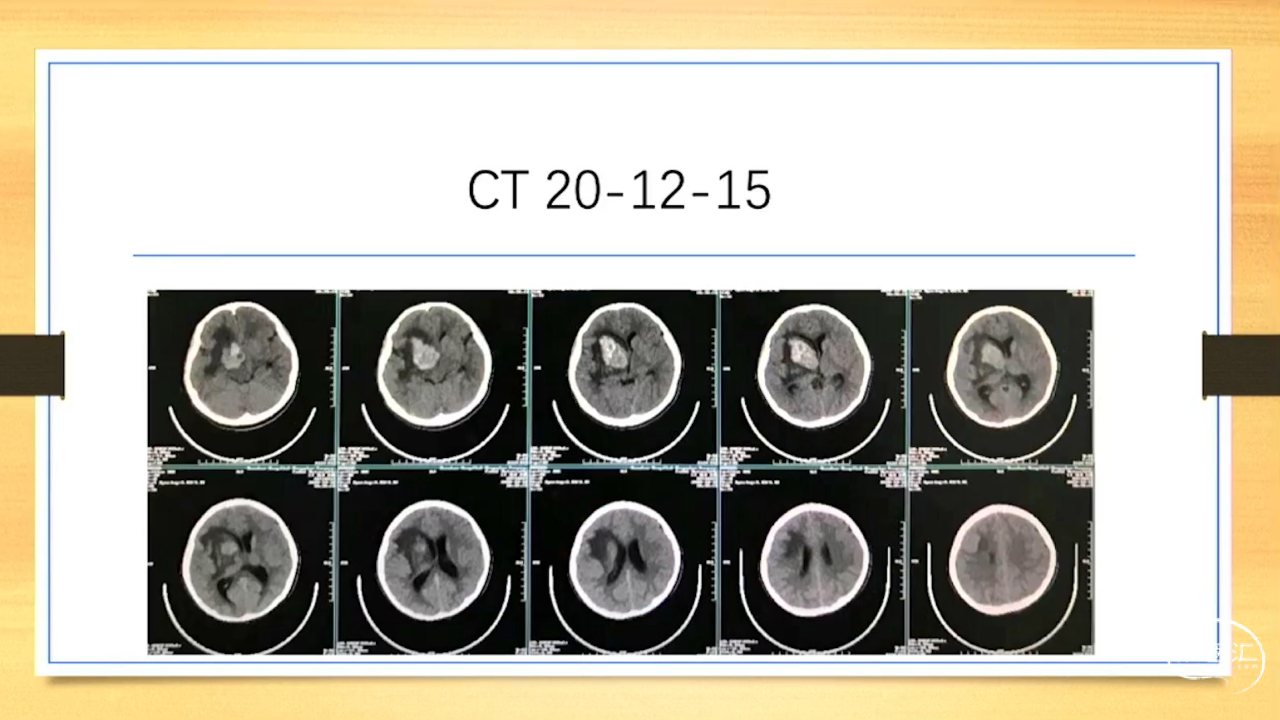

张荣教授:儿童颅内生殖细胞瘤的手术治疗

颅内生殖细胞肿瘤的治疗是手术、放疗、化疗、内分泌及其他多学科的整合治疗。及时、精准、合理的手术治疗是iGCT患者提高生存率、降低并发症、改善神经内分泌功能的关键。